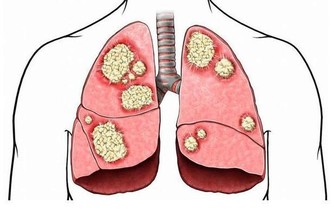

糖友買鞋,建議大半號

建議糖友最好在下午或傍晚去買新鞋,應選圓頭厚底、鞋碼大半號,且有鞋帶或搭扣的鞋子,這樣可方便調節腳的肥瘦情況。

還要注意選寬大、透氣性好的鞋子;鞋底要厚,彈性好,最好是防滑的牛筋底或膠底。

一開始穿新鞋時,千萬別穿太久,每次穿著20~30分鐘為宜。還應檢查鞋內壁和鞋墊上有無褶皺線頭,鞋內有無小石子等異物。